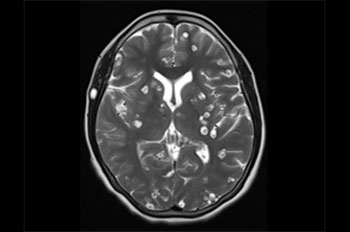

Nang sán thần kinh là nguyên nhân gây ra động kinh có thể phòng ngừa thường gặp nhất ở các nước đang phát triển, Đó là một nhiễm trùng thông thường của hệ thống thần kinh của con người và một mối quan tâm sức khỏe cộng đồng ngày càng tăng. Các triệu chứng của nang sán thần kinh có thể bao gồm đau đầu mãn tính, mù lòa, động kinh, viêm màng não và chứng mất trí.

8. Chẩn đoán nang sán thần kinh là khó khăn ở các vùng nông thôn(Diagnosis of neurocysticercosis is difficult in rural regions)

Chẩn đoán ca nghi ngờ về nang sán hiện nay đòi hỏi chụp cắt lớp vi tính (CT scans), các cơ sở này thường không có sẵn trong khu vực nông thôn, nơi mà căn bệnh này là phổ biến nhất, làm cho nó khó khăn để xác định và điều trị bệnh nhân. Điều quan trọng là để kiểm soát ký sinh trùng bằng cách tìm và điều trị những người bị tình trạng bệnh lý này và do đó tránh nguy cơ lây nhiễm.